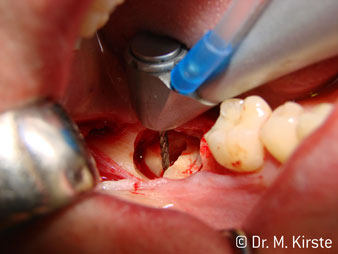

Le contre-angle avec tête angulée à 45° a surtout été choisi pour ses nombreux avantages. Les collègues qui exercent en chirurgie, et à qui cet instrument est principalement destiné, apprécieront très vite la possibilité de travailler efficacement dans des zones très étroites. En particulier, lors d’extractions de dent de sagesse (Ill. 2), où il n'y a pas besoin d’un grand angle d’écartement des tissus mous dans la région de la joue (Ill. 3). Pendant la préparation, une légère rotation de la tête de l’instrument permet un travail rapide et sans risque dans la zone rétromolaire.

En terme de rapidité, l'instrument peut atteindre jusqu’à 100 000 tr/min. Tandis qu'un spray très professionnel et une tête aux dimensions réduites répondent à toutes les exigences en matière de refroidissement et de visibilité de la zone de traitement.

Le contre-angle avec tête angulée à 45° est très agréable à utiliser. D’emblée on remarque que la partie travaillante de la tête imite l'angle de l’index et qu’ainsi le mouvement que vous souhaitez faire est simplement déplacé de deux ou trois centimètres, parallèlement à la pointe de l’instrument rotatif.“ (Ill. 1)

Ill. 1